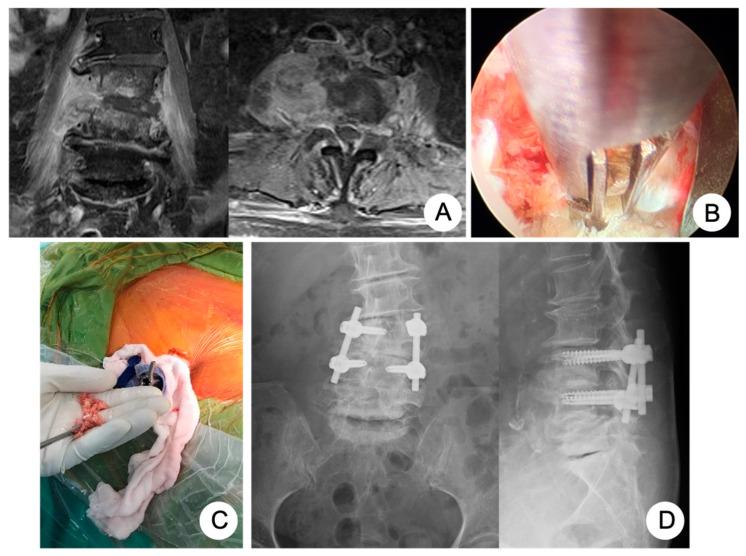

Background: Postoperative immunosuppression is associated with blood loss and surgical trauma during surgery and subsequently predisposes patients to increased morbidity. Spine endoscopic surgery has been accepted as an effective surgical technique with less surgical trauma and less blood loss for the complication of infectious spondylodiscitis. Therefore, the aim of this study was to investigate whether PEIDF could reduce the morbidity rates for patients with infectious spondylodiscitis. Methods: We launched a retrospective cohort study on the comparison of the perioperative prognosis between PEIDF and conventional open surgery for single-level lumbar infectious spondylodiscitis in patients with poor physical health (ASA ≥ 4) from 2014 to 2019. Results: Forty-four patients were included in this study. Fifteen of them underwent PEIDF, and the rest of the 29 patients were treated with open surgery. Less surgical blood loss (p < 0.001) and intraoperative transfusions (p < 0.001) with a better decline of CRP (p = 0.017) were statistically significant in patients receiving PEIDF. Patients undergoing conventional open surgery encountered more postoperative sepsis (p = 0.030), a higher qSOFA score (p = 0.044), and prolonged-time for CRP normalization (p = 0.001). Conclusions: PEIDF minimizes a poor postoperative outcome due to less surgical trauma, intraoperative blood loss, and the need for a blood transfusion.

术后免疫抑制与手术期间的失血和手术创伤有关,随后使患者更容易出现发病率增加的情况。脊柱内镜手术已被公认为是一种有效的手术技术,对于感染性脊椎椎间盘炎并发症而言,其手术创伤较小且失血较少。因此,本研究的目的是调查经皮内镜下椎间盘切除术(PEIDF)是否能降低感染性脊椎椎间盘炎患者的发病率。方法:我们开展了一项回顾性队列研究,比较了2014年至2019年期间身体健康状况较差(美国麻醉医师协会身体状况分级≥4级)的单节段腰椎感染性脊椎椎间盘炎患者接受PEIDF与传统开放手术的围手术期预后。结果:本研究纳入了44例患者。其中15例接受了PEIDF,其余29例患者接受了开放手术治疗。接受PEIDF的患者手术失血量较少(p<0.001)、术中输血较少(p<0.001),且CRP下降情况较好(p=0.017),差异具有统计学意义。接受传统开放手术的患者术后发生败血症的情况更多(p=0.030)、序贯器官衰竭评估(qSOFA)评分更高(p=0.044),且CRP恢复正常的时间更长(p=0.001)。结论:由于手术创伤较小、术中失血量较少以及输血需求较少,PEIDF可将不良术后结局降至最低。